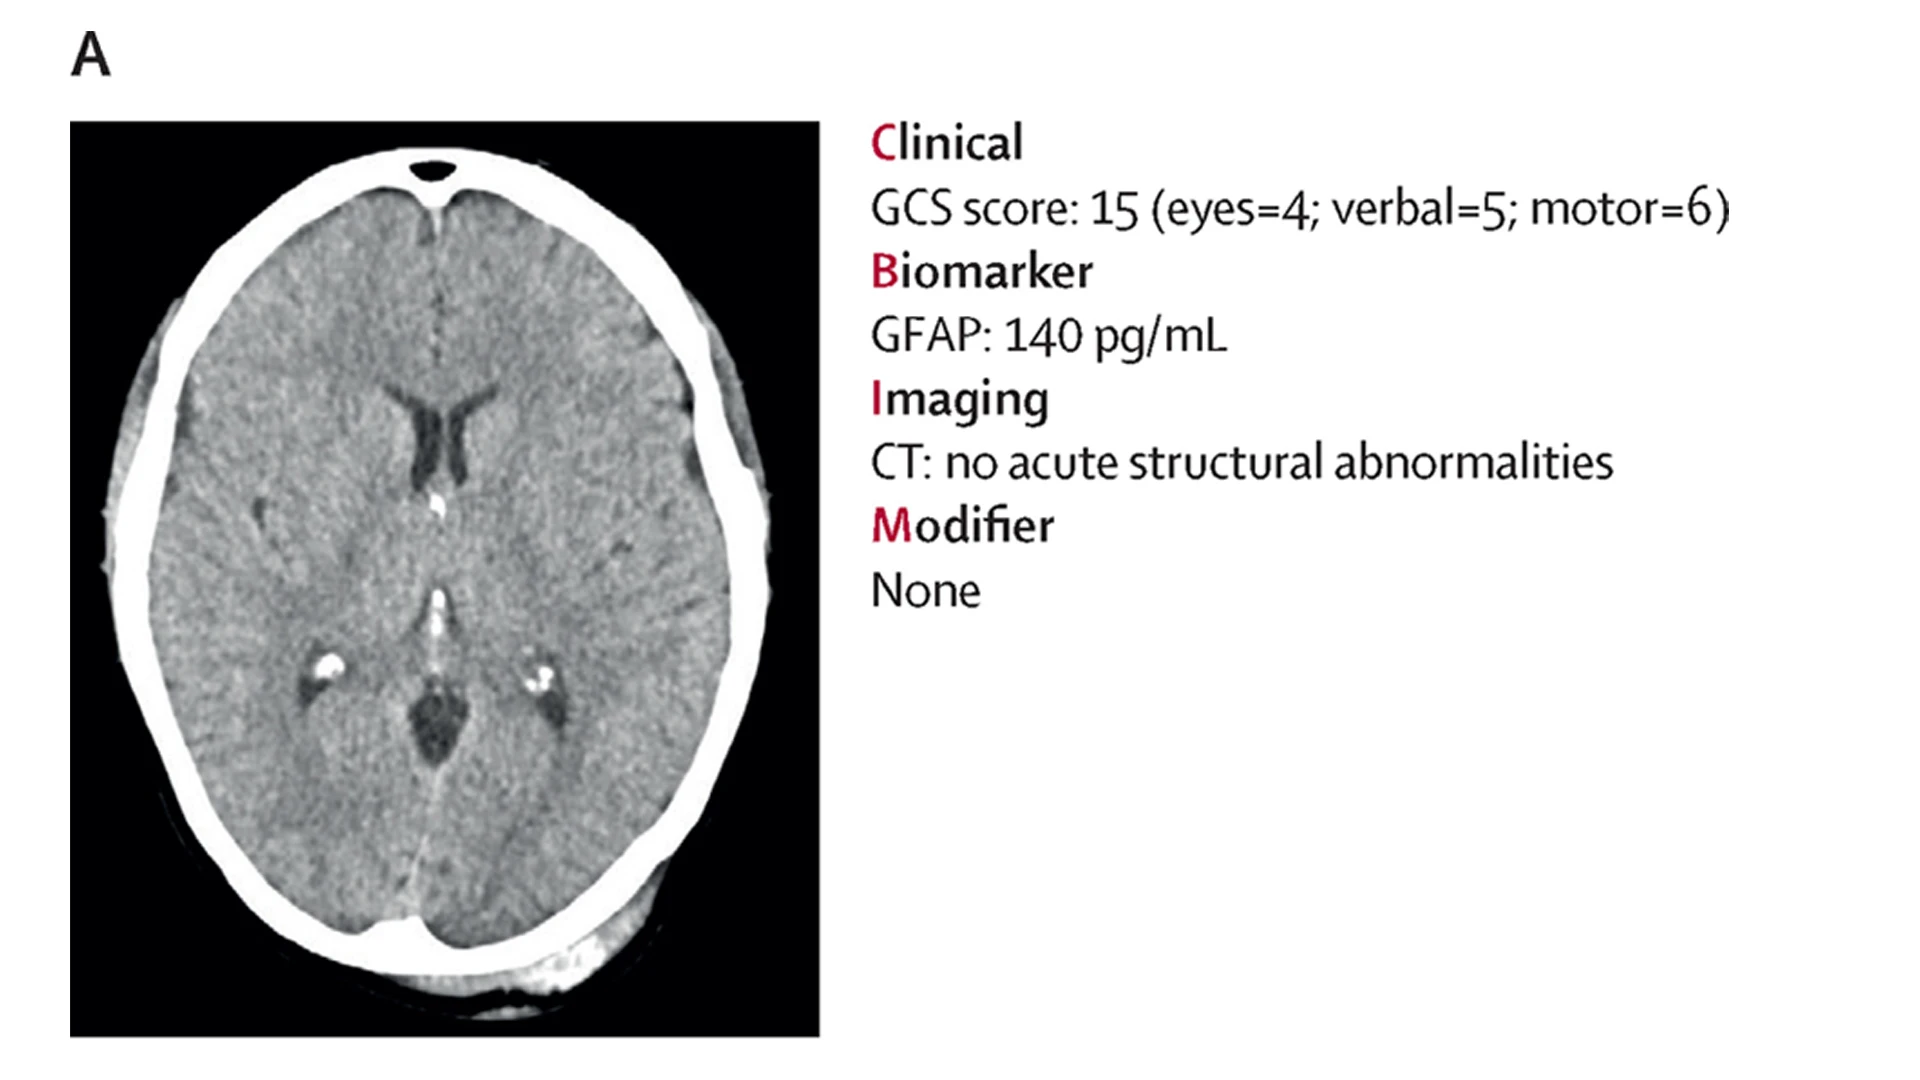

Dr. Dams-O’Connor, Director of the internationally recognized Brain Injury Research Center of Mount Sinai, is working with colleagues across the globe to take concrete action. She is co-leading an initiative, along with other experts in the field, to develop a clinical, biomarker, imaging, and modifier (CBI-M) framework for characterizing traumatic brain injury—a more holistic and comprehensive way of conceptualizing brain injury severity based on deeper clinical and biological phenotyping.

While GSC remains a foundational block of the proposed new classification system, developers worked diligently on a new multidimensional framework for improved characterization of TBI built on four “pillars,” each rooted in the latest science, technology, and clinical practice.

Clinical Pillar

Involves a clinical assessment of pupillary reactivity response based on one or both pupils. It also includes assessment of post-traumatic amnesia as an expanded clinical component, as well as evaluation of signs and symptoms such as duration of unconsciousness and/or altered mental state, cognitive function, vestibular-ocular function, and balance, as measured by validated clinical assessment tools, to refine prognosis and recommendations for follow-up care.

Biomarker Pillar

Blood biomarkers are an exciting new tool for informing triage, diagnosis, and treatment of TBI, providing a clinically accessible window into pathophysiology. Although biomarker assays for TBI are not yet in widespread use, developers of the new framework recommended acute post-TBI measurement of one or more of the following biomarkers: glial fibrillary acidic protein (GFAP), ubiquitin C-terminal hydrolase L1 (UCH-L1), and S100 calcium-binding protein B (S100-B). Both GFAP and UCH-L1 have been cleared by the U.S. Food and Drug Administration (FDA) based on scientific evidence supporting their utility in TBI diagnosis and care management.

Imaging Pillar

Because neuroimaging is an important source of information about degree and neuroanatomical location of brain injury, this working group focused on use of a computed tomography (CT) scan within the first 24 hours of injury. While its experts recognized that MRI is more sensitive than CT and can provide additional information such as diffusion metrics, they also knew that CT is the most commonly used and readily accessible imaging modality in acute care. Recommendations were also made for documentation of lesion volume, presence and sequelae of mass effect, and other common neuroimaging findings that can be informative for providing personalized care.

Modifier Pillar

It is well established that the clinical presentation, recovery, and outcome following TBI can be influenced not only by biomechanical and physiological features of the injury, but by psychosocial and environmental factors that can modify the effects of the injury. Thus, this pillar includes injury-related factors, patient-related factors, and community and society-related factors. The latter is particularly novel for the field as it encourages consideration of things such as geographic location, cultural-linguistic background, and pre-injury mental health so the care teams can leverage strengths and identify and overcome potential barriers to optimize care and recovery.